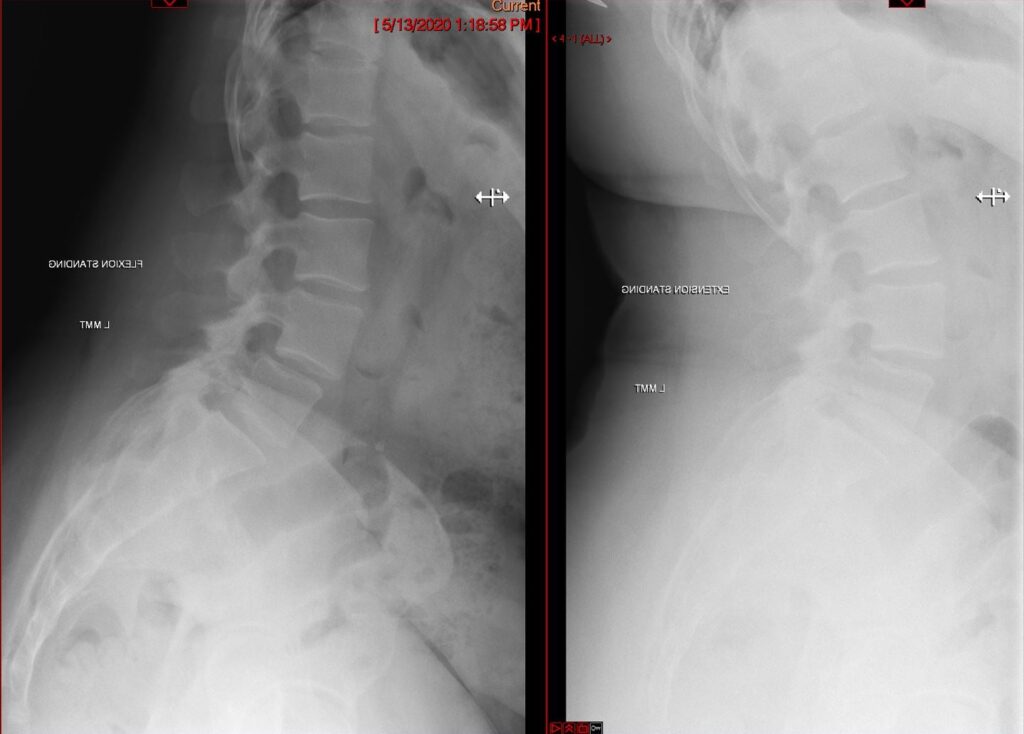

Oblique Lumbar Interbody Fusion